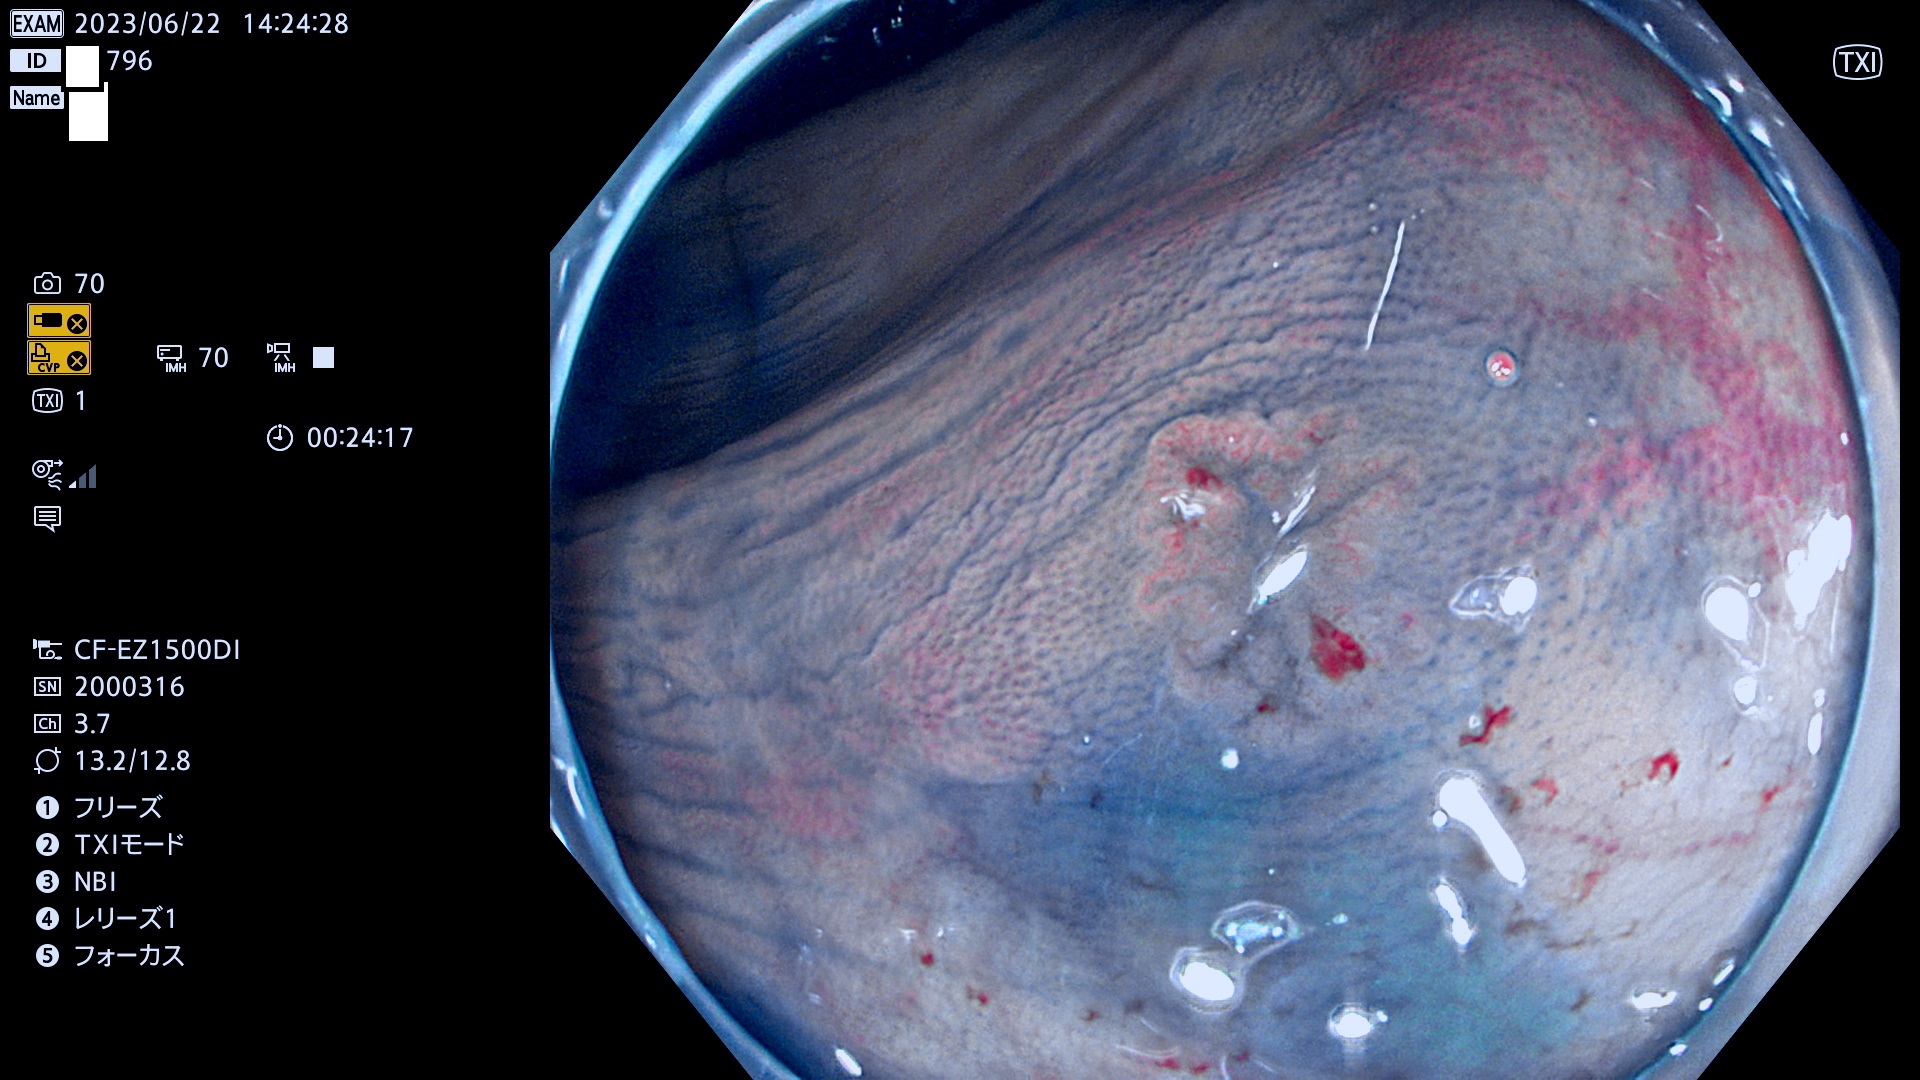

「表面型腫瘍」の中で、完全に平坦な物をUb、陥凹している物をUcと呼びます。平坦隆起型(Ua)よりも、発見が難しく危険な病変です。このタイプの発見率は「腺腫発見率」よりも、遥かに重要な意義があります。

抽出の対象期間 2023年6月22日(木)〜25(日)の4日間(48件の検査)5件

当サイトは以前は「腺腫発見率」を定期公開していました。「Ub,Uc発見率」は検査の品質指標として、遥かに重要であり、医師にとっても非常にシビアです。定期公開の目的は、検査精度の維持です。これにより医師は常に、「Ub,Ucを見つける!」という緊張感・動機をもって、検査に望む訳です(Ub,Ucを探せば、他の形態の病変は容易に見つかります。このような趣旨なので形態診断学的には厳密ではありません)。